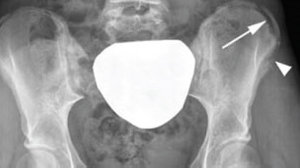

The other more common avulsion injury, which often is difficult to determine on radiographs, is an injury to the hip or pelvis. Figure 2 demonstrates an avulsion fracture of the iliac crest. Management of hip and pelvis apophysitis depends on the degree of pain and disability of the athlete. If walking and standing are painful or the athlete is limping, then protected weight-bearing on crutches may be necessary initially.

FIG 2 Iliac crest avulsion fracture on AP view of pelvis. Note widening of the apophysis (arrows) compared with opposite side.

Rest should be followed by a period of rehabilitation including stretching and strengthening of the hip and abdominal muscles. Once the athlete achieves full, pain-free range of motion and strength, a gradual return to sport may begin. Athletes can expect return to full participation in 4-6 weeks, depending on the initial degree of pain and disability and compliance with rest and rehabilitation. As many clinicians know, compliance can be difficult for the athlete, and support from coaches and even parents can be challenging.9-10